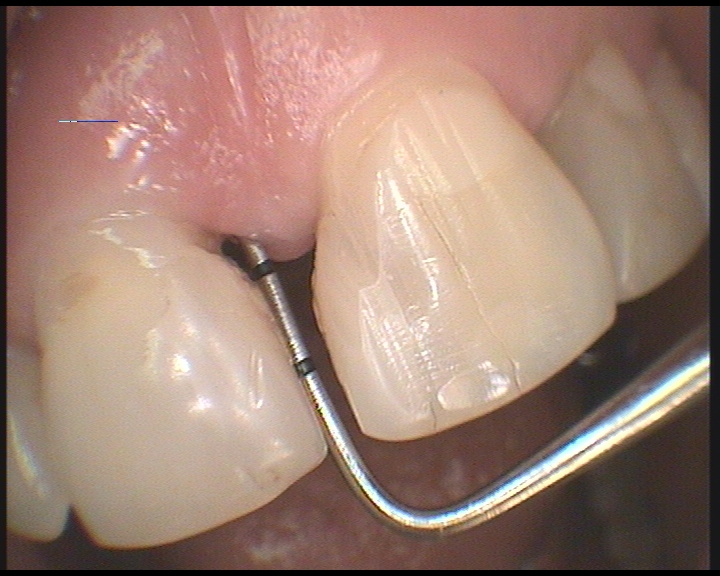

V našem stomatologickém centru se využívá pro ošetření kořenových kanálků operační mikroskop a příslušné mikroskopické techniky. Důvodem, proč používáme operační mikroskop je fakt, že dřeňová dutina, ze které vystupují kořenové kanálky bývá obvykle malá, málo přehledná a těžko ji lze běžným ordinačním světlem dostatečně osvětlit. Operační mikroskop umožňuje mnohonásobné zvětšení dřeňové dutiny i vstupy do jednotlivých kanálků. Lékař pak vidí konkrétní detail o velikosti asi jako kopací míč. Práce je pak mnohem přesnější a detailnější.

Operační mikroskop navíc přes svoji optiku svítí do dřeňové dutiny silným LED světlem, což je pro přesnost a kvalitu práce velmi důležité. Tím dosahujeme při ošetření kořenových kanálků velmi dobré a hlavně dlouhodobé úspěšnosti . Navíc nám to umožňuje ošetřovat i zuby s komplikovaným kořenovým systémem , které jsou v běžné ordinaci bez mikroskopu prakticky neošetřitelné a musí se extrahovat (vytrhnout).